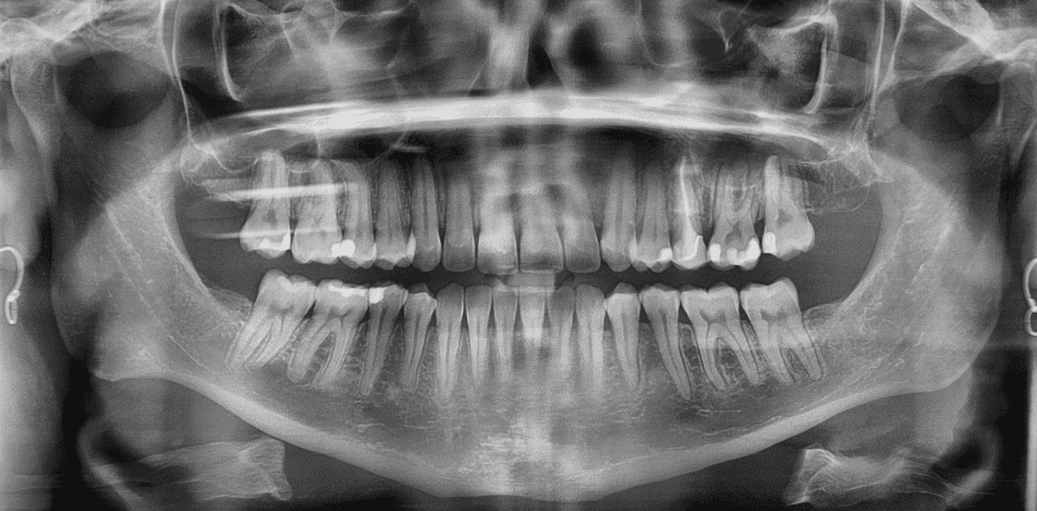

X-RAYS